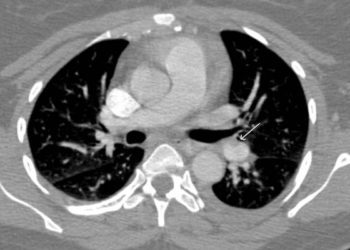

In-Depth [cross-sectional study]: This study was conducted from March 2012 to October 2014 at 11 Italian hospitals. Patients seen in the emergency department (n = 2584) and subsequently admitted to the hospital (n = 717) were considered for the study. Reasons for admission were often failure to identify cause of syncope, fall related trauma, or high suspicion of cardiac related cause of syncope. Patient workup included Wells criteria questions for determining pretest probability of pulmonary embolism, D-dimer assay, chest X-ray, electrocardiogram, and routine blood testing. If indicated, patients received prophylactic anticoagulation. Based on patient history and D-dimer results, patients included in the study (n = 560) were classified as “likely” of “unlikely” to have a pulmonary embolism. No further pulmonary embolism workup was done for the “unlikely” group (n = 330, 59%), while those in the “likely” group (n = 230, 41%) were scanned with computed tomographic pulmonary angiography or VQ regimen as clinically appropriate. Pulmonary embolism was determined if CT scan showed an intraluminal filling defect or a VQ scan showed a perfusion defect of >75% of a normally ventilated segment. Pulmonary embolism was detected on 40% of CT scans (72/180), 49% of VQ scans (24/49), and in one autopsy performed (1/1). Overall, pulmonary embolism was detected in 17.3% (97/560) of patients in the study. On CT scans, emboli were located in the main pulmonary artery (30/72), lobar arteries (17/72), segmental arteries (19/72), and subsegmental arteries (5/72). Of patients presenting with syncope of undetermined origin (n = 205), pulmonary embolism was detected for 52 (25.4%; 95%CI 19.4 to 31.3). For 355 patients whose syncope was thought to be from another cause, pulmonary embolism was detected in 45 (12.7%; 95%CI 9.2 to 16.1).